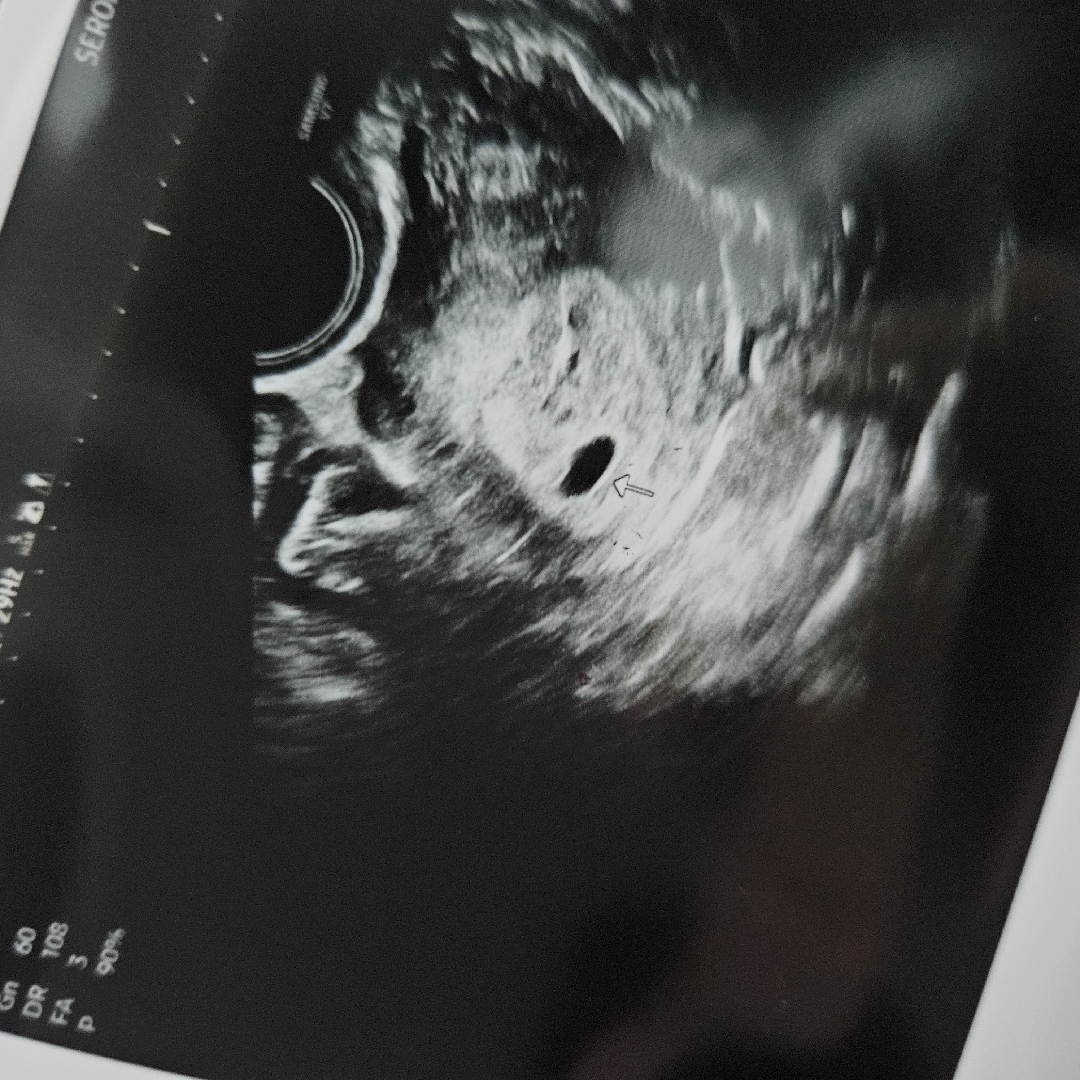

어제 아기집보고왔어요! 막생기준으로 1주일 정도 늦는다고 하는데 복통이랑 피비침이 약간 있어서 질정제 처방받았네요 찐친들한테만 알려주고 공개 전인데 입이 간지러워서 여기까지 왓어요 잘 자라고 있는거겠죠?ㅠㅠㅠ

와 4주1일인데 크네용!!👍🏻

큰거에요??ㅎㅎㅎ너무 걱정이였는데 감사합니다

저는 아주 콩알만해요,,